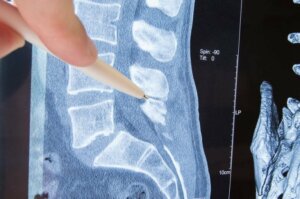

من المحتمل أن تكون قد سمعت عن مصطلح الاعتلال العصبي من قبل، ولكنك لا تعرف الكثير عن الحالة. ولفهمها، من المهم معرفة القليل عن العمود الفقري.

العمود الفقري هو هيكل عظمي يتكون من فقرات، وهو ما يحمي العظام ويسمح بالحركة الحرة. تحتوي هذه الفقرات على ثقوب على كلا الجانبين، والتي يخرج منها الأعصاب التي تصل إلى أجزاء الجسم المختلفة.

جزء العصب الذي يخرج من الفقرات يُعرف باسم “جذر العصب”. الاعتلال العصبي يظهر عند تعرض جذور الأعصاب للضغط.